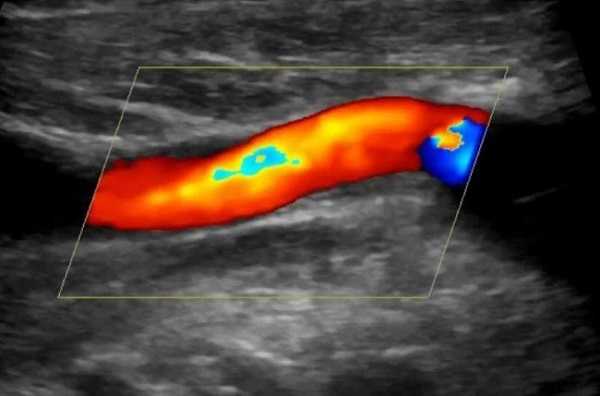

Исследование объединяет построение 2D-изображений и анализ целевых сосудов. Принцип регистрации данных УЗ-аппаратом заключается в разнице получения сигналов от статичных и движущихся объектов. Первые видны на мониторе в серой шкале, вторые - как участки красного и синего цветов, показывающие направление кровотока. Скорость последнего позволяет судить о выраженности окклюзии и количестве зон со сниженной перфузией.

Технология не представляет возможности измерить диаметр просвета сосуда в пораженном участке, в связи с чем были разработаны схемы, где результаты УЗДГ соотносят с определенной степенью стеноза, подтвержденной данными ангиографии.

В большинстве случаев исследование проводят с целью уточнения наличия или отсутствия атеросклеротических бляшек, уменьшающих диаметр просвета сосудов. Отложения продуктов липидного обмена чаще находят в области деления кровеносных каналов, или бифуркаций, ОСА на внутреннюю и наружную ветви. Высокая степень нестабильности пристеночного образования и стеноз артерии в пораженном сегменте создают угрозу развития инсульта, в том числе транзиторной ишемической атаки.